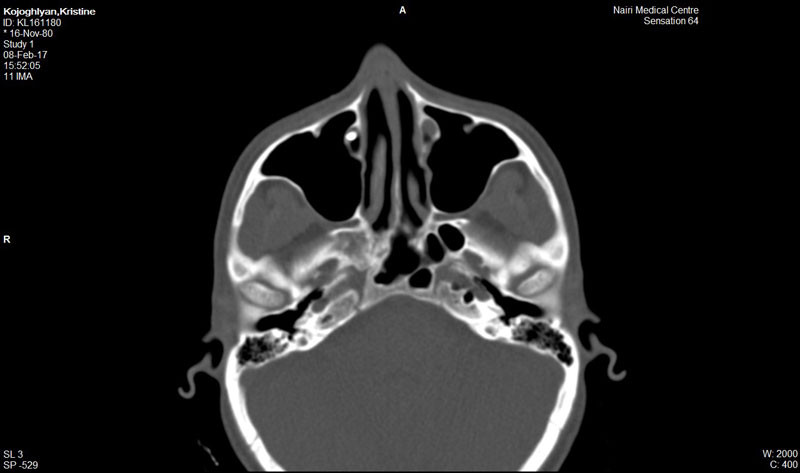

Հայաստանում միայն «Նաիրի» ԲԿ-ի Աչքի կլինիկայում է կոնտրաստային դակրիոգրաֆիա կոչվող ինովացիոն մեթոդով ճշգրիտ որոշվում արցունքատար խողովակների նեղացման տեղադրությունը եւ աստիճանը: